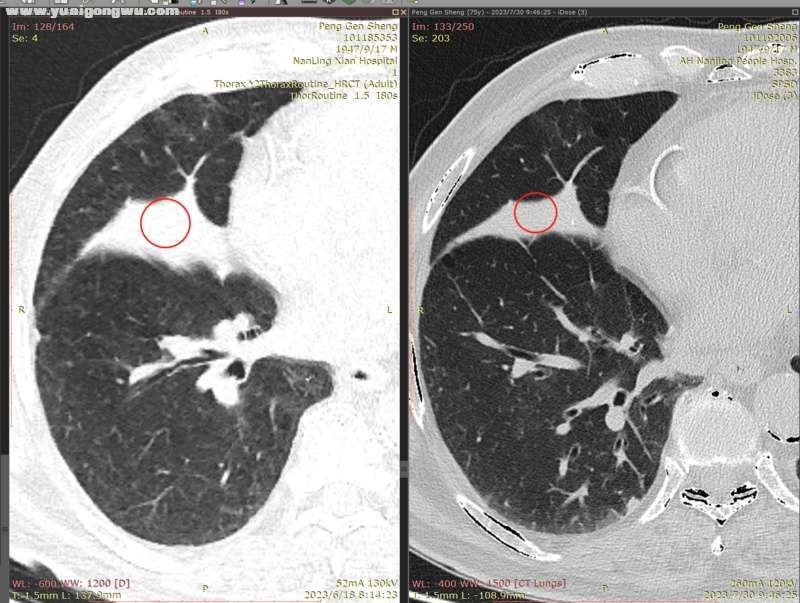

6月3日~7月29日,单用安罗替尼12mg(3周期),6月18日CT显示左肺主病灶稍缩(主病灶62mmx57mm);因近期有一点点吸不上气的感觉(吸氧后有缓解,其他身体体征正常,体感良好),7月30日CT显示左肺主病灶稍增大(主病灶68mmx62mm)。- L* L' w9 C: J7 b

影像科医生将7月30日的胸部CT,和6月18日的胸部CT电子影像对比分析如下:

: v& _. J  {' _( E1 `) |4 A: L* ^         1、左肺上叶主病灶(肿块),7月30日复查较2023.6.18略增大,如图红圈所示,局部边缘饱满(图1);: O% K* B! J8 F9 Q9 t8 j3 d

2、右肺多发小结节,前面两枚之前重点关注的结节(有时变大有时变小),这次复查略微变小(图2~5;+ }% G% E$ F0 e  U; {- |' V' B

* R5 w. e) k/ [9 Y( L' s' h* x* n7 d        以下为近两次CT影像的对比分析。7 Z8 B" @7 n7 B# ?+ K" ?( E( {) v